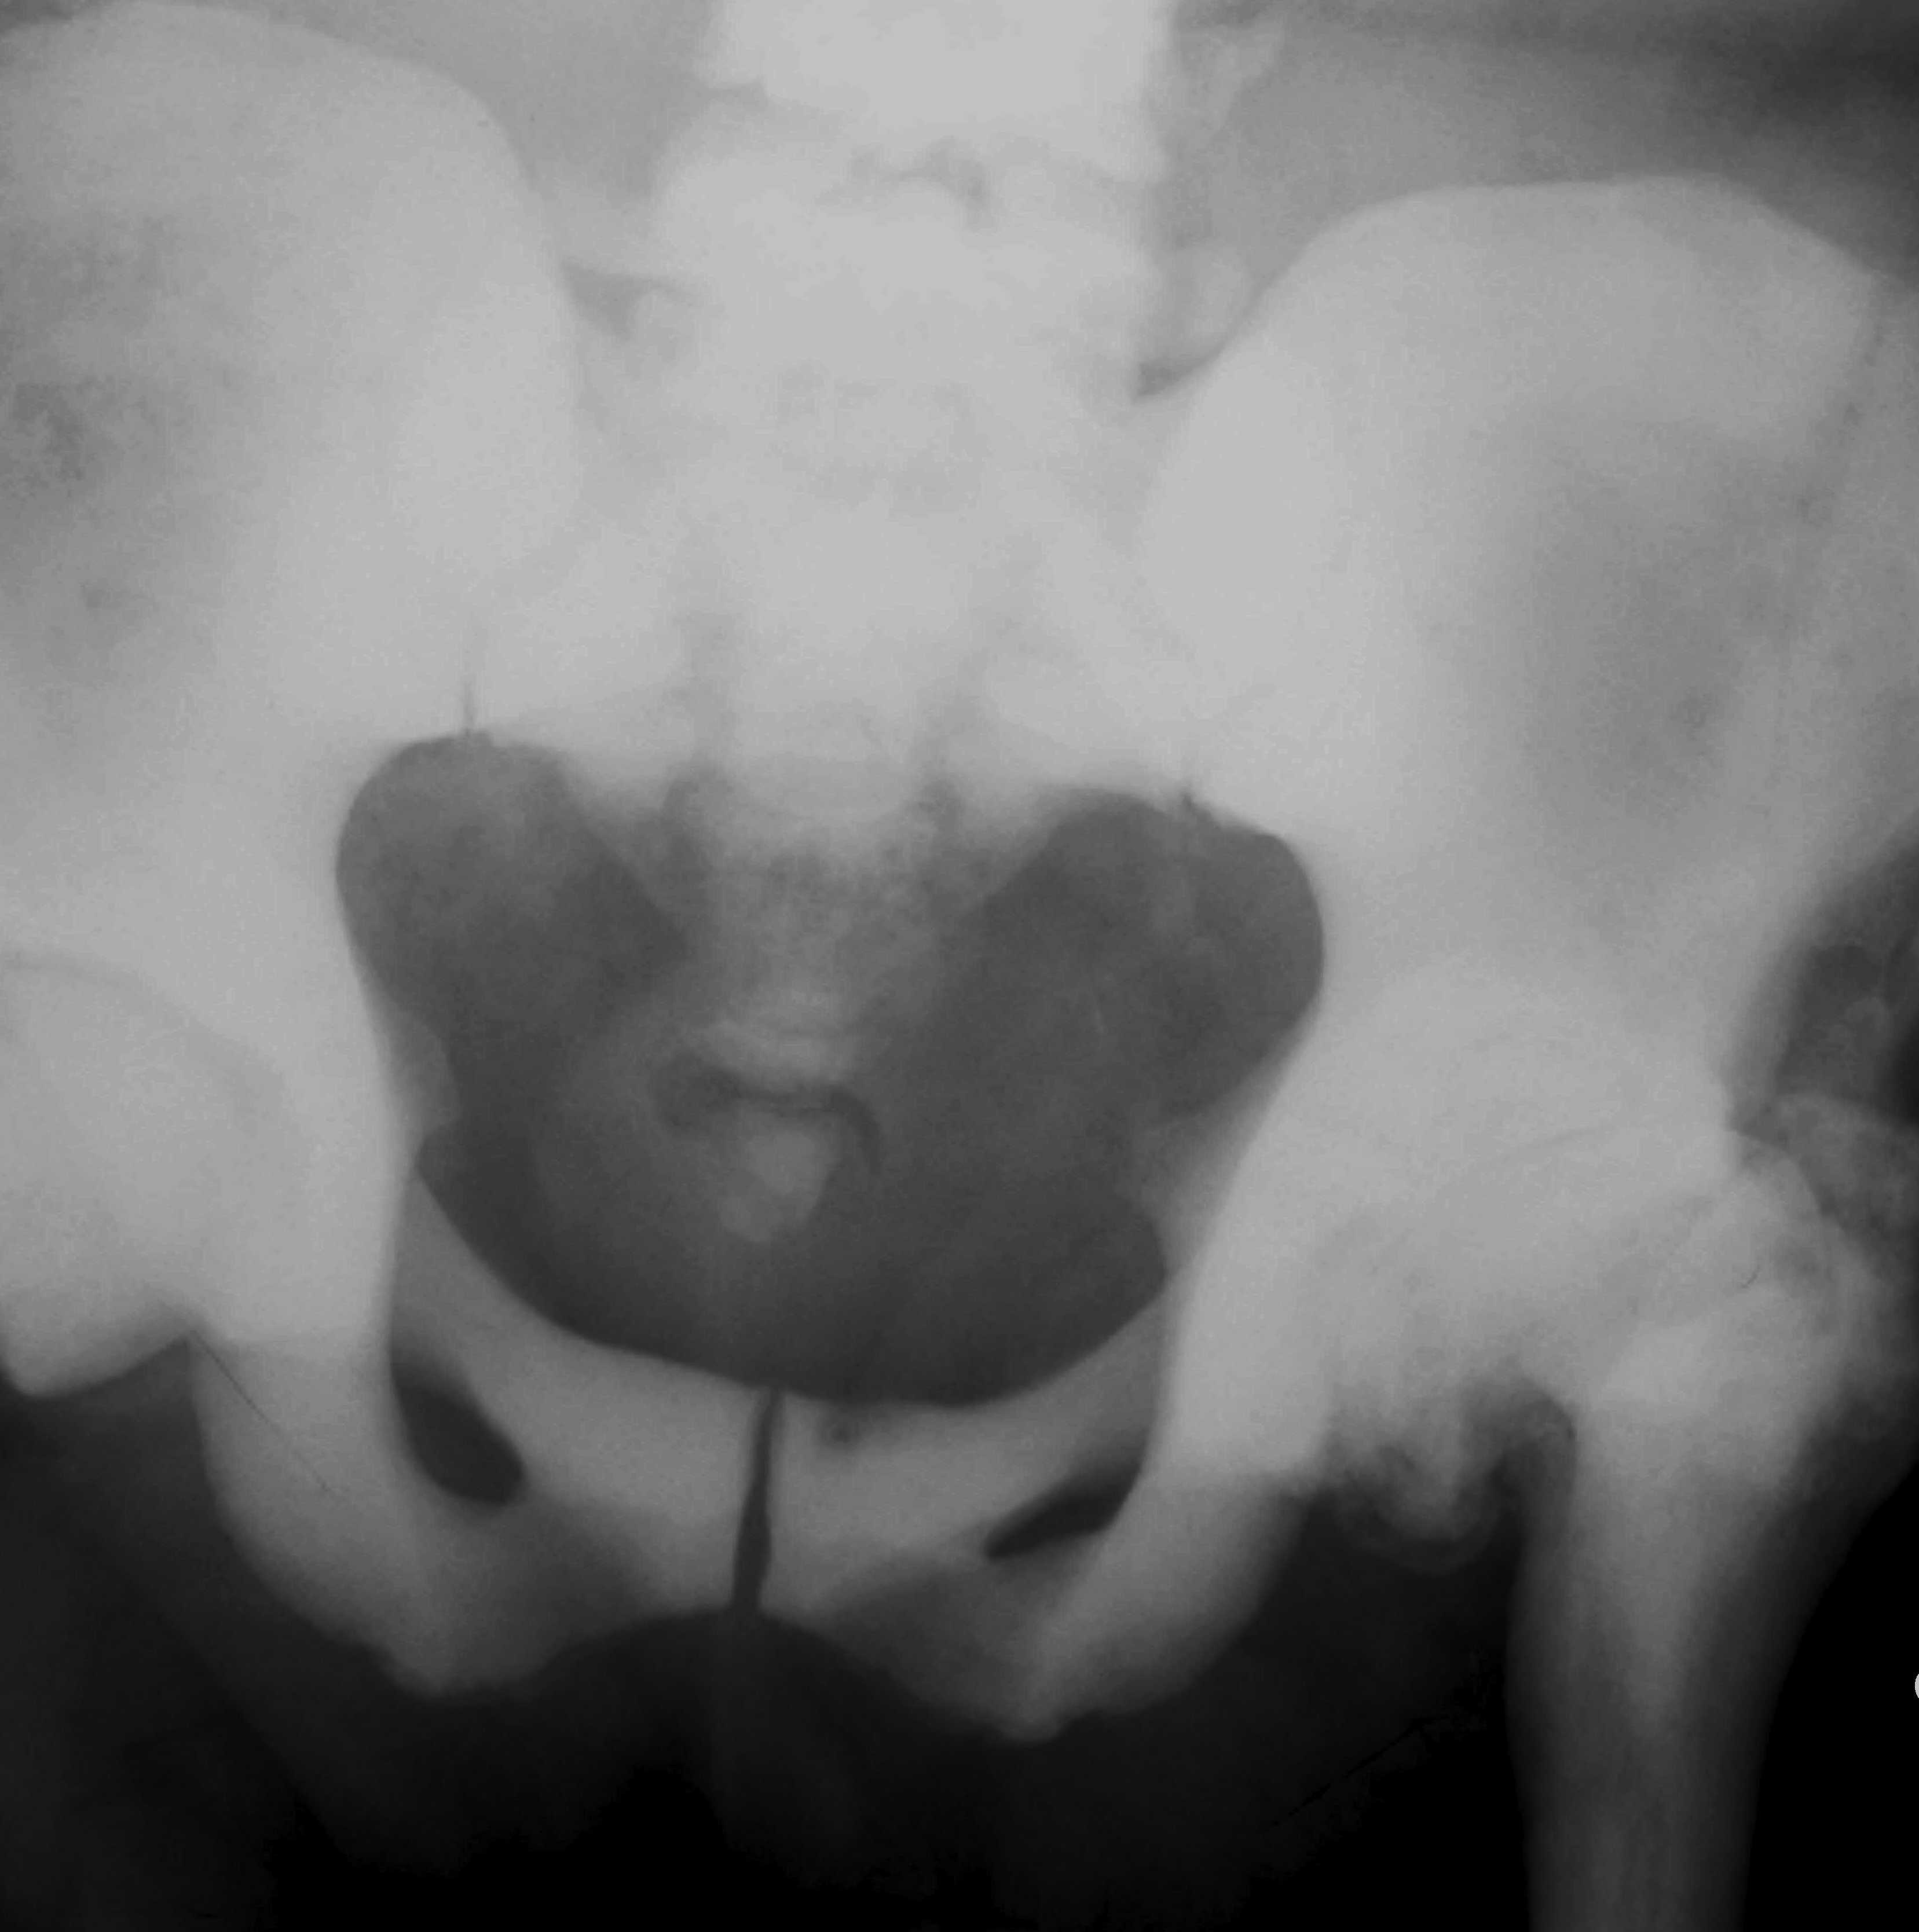

X-ray

Generalised sclerosis

- subchondral sclerosis in pelvis

Endobone

- bone within bone

- failed resorption of primary spongiosa

Vertebral end plate thickening

- rugger jersey vertebrae

Erlenmeyer flask deformity

- widened club like metaphysis

- in children

Transverse banding of metaphyses